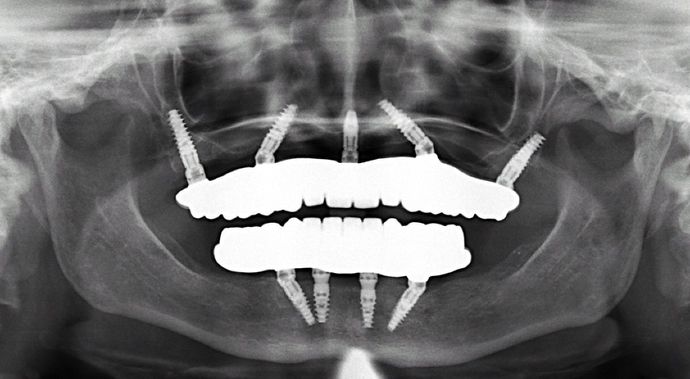

All-on-4/ Full Mouth Dental Implants / Teeth in a Day: Case 2-MS- Upper and lower All-on-4 bridges

This grandmother had a teeth grinding habit and had mouth full of cavities, gum disease, reduced bone and failing teeth and wanted the best possible result as she was also dissatisfied with her smile.

Procedures : extractions, implants, All on 4 , Teeth in a day, no bone grafting and full mouth reconstruction with monolithic zirconia bridges.